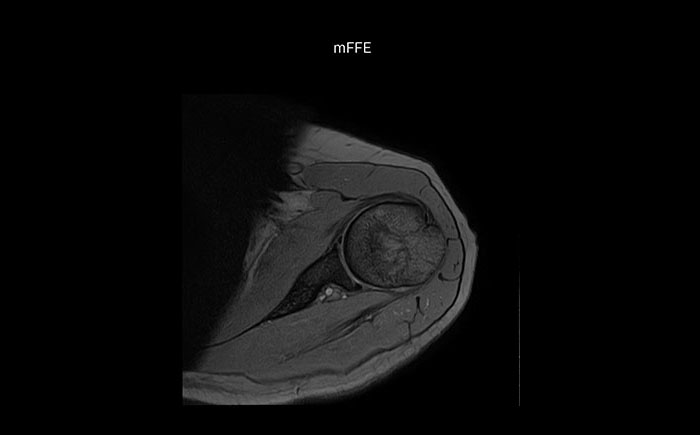

The Prodiva shoulder coil is very flexible and has large coverage, which makes good positioning easier, and that contributes to the superb image quality and high SNR that we get in our shoulder exams.